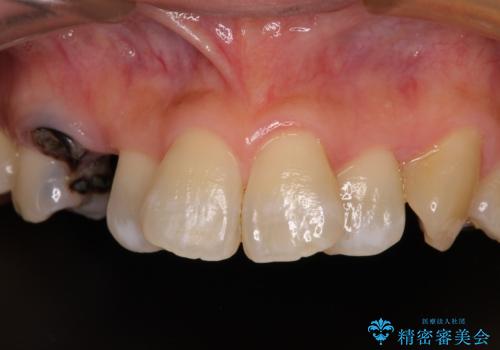

- 奥歯が咬みにくいことを主訴に来院された患者様です。

奥歯以外にも、全体的に大きな問題を抱えていらっしゃったので、全顎的な治療を行うこととしました。

1回の診療時間を長く取ることで、2回目の診療後にはすべてを仮歯にすることができ、長年気にされていた前歯の見た目を速やかに改善することができました。

オールセラミッククラウンによってとても自然に仕上がり、また、安定した咬み合わせとなったことで、患者様には大変満足していただきました。